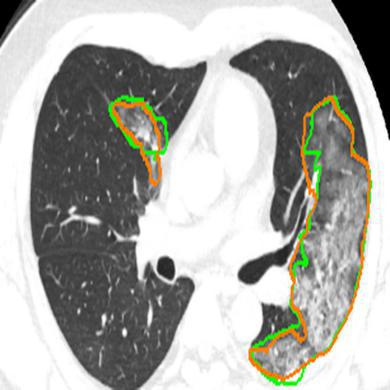

The novel coronavirus disease 2019 (COVID-19) characterized by atypical pneumonia has caused millions of deaths worldwide. Automatically segmenting lesions from chest Computed Tomography (CT) is a promising way to assist doctors in COVID-19 screening, treatment planning, and follow-up monitoring. However, voxel-wise annotations are extremely expert-demanding and scarce, especially when it comes to novel diseases, while an abundance of unlabeled data could be available. To tackle the challenge of limited annotations, in this paper, we propose an uncertainty-guided dual-consistency learning network (UDC-Net) for semi-supervised COVID-19 lesion segmentation from CT images. Specifically, we present a dual-consistency learning scheme that simultaneously imposes image transformation equivalence and feature perturbation invariance to effectively harness the knowledge from unlabeled data. We then quantify the segmentation uncertainty in two forms and employ them together to guide the consistency regularization for more reliable unsupervised learning. Extensive experiments showed that our proposed UDC-Net improves the fully supervised method by 6.3% in Dice and outperforms other competitive semi-supervised approaches by significant margins, demonstrating high potential in real-world clinical practice.